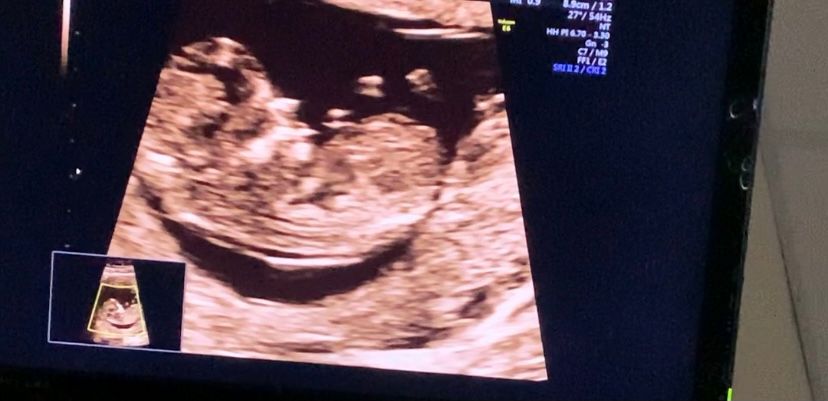

Девочки , мальчик или девочка?

12 Недель , сказали половой бугорок кверху , посмотрите пожалуйста :)

😂😂😂 мне кажется, на последнем фото в уголке фигура из 3х пальцев . Вообще кверху парень, а девочка- он параллелен тельцу. Но это же опять из теории и прочитанного.